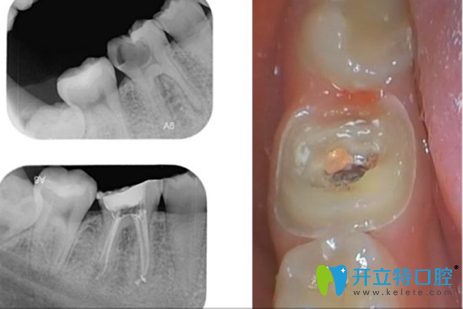

2、根管治療+烤瓷牙冠+補牙+洗牙

地點:歡樂口腔華貿(mào)分院  醫(yī)生:張醫(yī)生

歡樂口腔華貿(mào)分院根管治療+烤瓷牙冠+補牙+洗牙綜合治療案例

顧客點評:我的牙體碎裂有一年多,在其他掛不上號,朋友正好推薦, 來試試。結(jié)果非常滿意,張醫(yī)生超級棒,一步一步把牙齒問題解決。 冠戴上就可以正常吃飯了。推薦小朋友&不喜歡看牙的大人來。